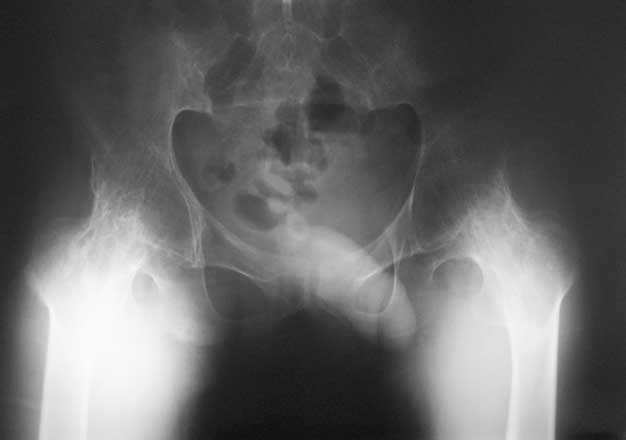

Уважаемые коллеги, в отделении находится пациент 28 лет, страдающий ревматоидным артритом с детства. В настоящее время  основной проблемой для него являются тазобедренные суставы - костный анкилоз в положении сгибания около 80 град. Выраженная атрофия мышц. ограничение движений в коленных суставах.Суставы "замкнулись" со слов пациента около 5 лет назад. Пациент работает (сидячая работа, высшее образование). Все проблемы перечислять не буду. Основное -сложности с ходьбой,самообслуживанием, эстетика и т.д.  Вопросы:

1. Насколько возможно и целесообразно эндопротезтрование в такой ситуации?

Наш план - остеотомия на уровне шейки бедра, иссечение капсулы, субспинальная тенотомия, а так же приводящих мышц, фасции,  после чего - дозированное разгибание  АВФ "таз -бедро".

Насколько это реально. кто-нибудь имел подобные случаи, возможно ли разогнуть бедро без неврологии, другие варианты релиза?

Имя     : Р-фас.jpg

Тип     : image/jpeg

Размер  : 10328 байтов

Описание: отсутствует

Url     : http://weborto.net:8080/pipermail/ortho/attachments/20080911/a1ff6af2/attachment-0013.jpg